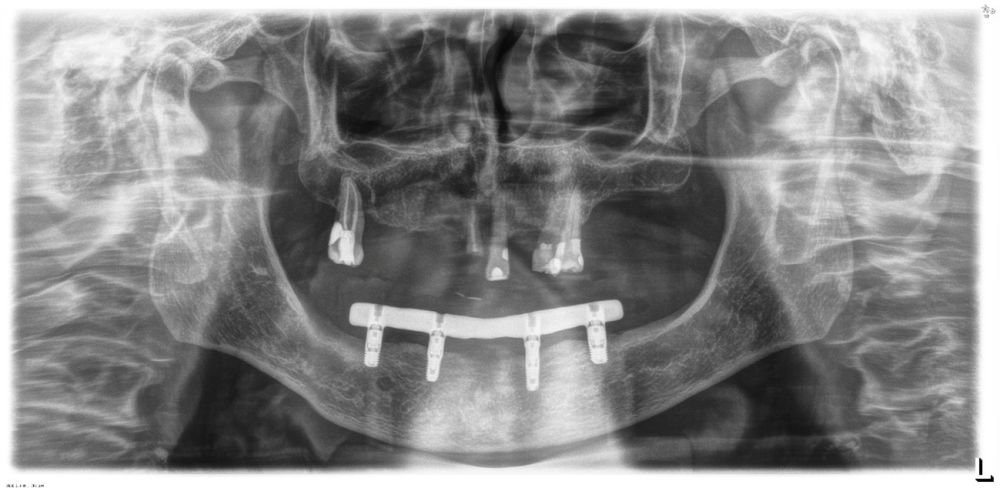

Todas las rehabilitaciones protésicas siguieron un mismo protocolo estandarizado. Una vez completada la cirugía, se procedió a la carga inmediata mediante una prótesis provisional atornillada sobre pilares transepiteliales, diseñada para distribuir las cargas de forma progresiva durante los primeros meses. Pasado un intervalo de entre seis y doce meses, y tras confirmar la estabilidad clínica y radiográfica de los implantes, se elaboró la prótesis definitiva. Esta consistió en una estructura metálica, revestida con resina acrílica, conformando una prótesis híbrida atornillada que mantenía el mismo esquema funcional que la provisional. El control radiográfico se llevó a cabo mediante radiografías panorámicas estandarizadas, realizadas siempre con el mismo sistema de posicionamiento reproducible, que incluía referencias en el suelo para los pies y apoyos simultáneos en glabela y mentón, con el fin de mantener constantes las relaciones angulares y minimizar la distorsión entre visitas. La medición de la pérdida ósea marginal se efectuó sobre la última radiografía panorámica obtenida bajo este protocolo de estandarización. Una vez digitalizada la imagen, se procedió a su calibración mediante un software específico (Digora for Windows, SOREDEX Digital Imaging Systems), utilizando como referencia una longitud conocida (el propio implante). Tras incorporar dicho valor, el programa corregía la magnificación inherente de la técnica panorámica, permitiendo realizar mediciones lineales exactas y exentas de distorsión. La pérdida ósea marginal se cuantificó en las superficies mesial y distal de cada implante, expresándose siempre como valor absoluto.

Fueron evaluadas 26 prótesis híbridas mandibulares soportadas por cuatro implantes, lo que genera un total de 104 implantes. De estas 26 prótesis, 12 fueron prótesis sobre implantes cortos (longitud < 10 mm) y 14 como prótesis sobre implantes largos (≥ 10 mm). La muestra presentó un claro predominio femenino, con 21 mujeres (80,8%) y 5 varones (19,2%). La edad media de los pacientes fue de 69,7 ± 11,2 años en el momento del inicio del estudio. A nivel de implante, la densidad media del hueso receptor fue de 866.16 ± 146.35 HU, mientras que el torque medio de inserción alcanzó 47.88 ± 9.01 Ncm. En cuanto a los diámetros de los implantes, en el grupo de los implantes cortos, el más frecuente fue el de 3,5 mm con un 56,5% de los casos, mientras que en el grupo de los implantes largos el diámetro predominante fue para 3,5 y 3,75 mm con un 32,1% para cada una de las categorías (Figura 1.a). En cuanto a la distribución de las longitudes, en el grupo de los implantes cortos, la más frecuente fue 7,5 mm con un 54,3% mientras que en los implantes largos la más frecuente fue 10 mm (47,2%) (Figura 1.b).

Todos los implantes fueron rehabilitados con prótesis híbridas atornilladas, sobre transepitelial. Este transepitelial presentó una altura entre 1 y 4 mm siendo el más frecuente 3 mm en el 75,8% de los casos. La distribución de las alturas de los transepiteliales se muestra en la Figura 2.

El análisis global de los 99 implantes reveló una pérdida ósea marginal media de 0,77 ± 0,26 mm en la superficie mesial y 0,79 ± 0,29 mm en la distal, valores que se mantuvieron dentro de los rangos considerados clínicamente aceptables para rehabilitaciones mandibulares. Cuando los implantes se categorizaron según su longitud, se observaron diferencias claras entre ambos grupos. Los implantes cortos (<10 mm) mostraron una pérdida ósea mesial media de 0,61 ± 0,23 mm y distal de 0,56 ± 0,22 mm, mientras que los implantes largos (≥10 mm) presentaron pérdidas significativamente mayores (mesial: 0,92 ± 0,19 mm; distal: 0,99 ± 0,17 mm). Dado que las pruebas de normalidad (Shapiro–Wilk) mostraron una distribución no normal en todos los grupos (p < 0,001), se aplicó la prueba no paramétrica de Mann–Whitney U. Los resultados confirmaron diferencias estadísticamente significativas tanto en la pérdida ósea mesial (U = 2068,5; p < 0,001) como en la distal (U = 2247,0; p < 0,005), indicando que los implantes cortos presentaron un comportamiento óseo más favorable que los implantes largos a lo largo del tiempo. Durante el tiempo de seguimiento que fue de media de 12,2 años (+/- 4,4; rango 6-23 años) no se objetivaron fracasos en ninguno de los implantes por lo que la supervivencia acumulada fue del 100%. El análisis del periodo de seguimiento mostró diferencias claras entre ambos grupos. Los implantes largos (≥10 mm) presentaron un tiempo medio de función de 14,1 ± 4,2 años (rango: 9–23 años), mientras que los implantes cortos (<10 mm) registraron un seguimiento significativamente menor, con una media de 9,8 ± 2,7 años (rango: 6–15 años). En las Figuras 3- 10 se muestran dos casos incluidos en el estudio, uno de cada situación descrita.